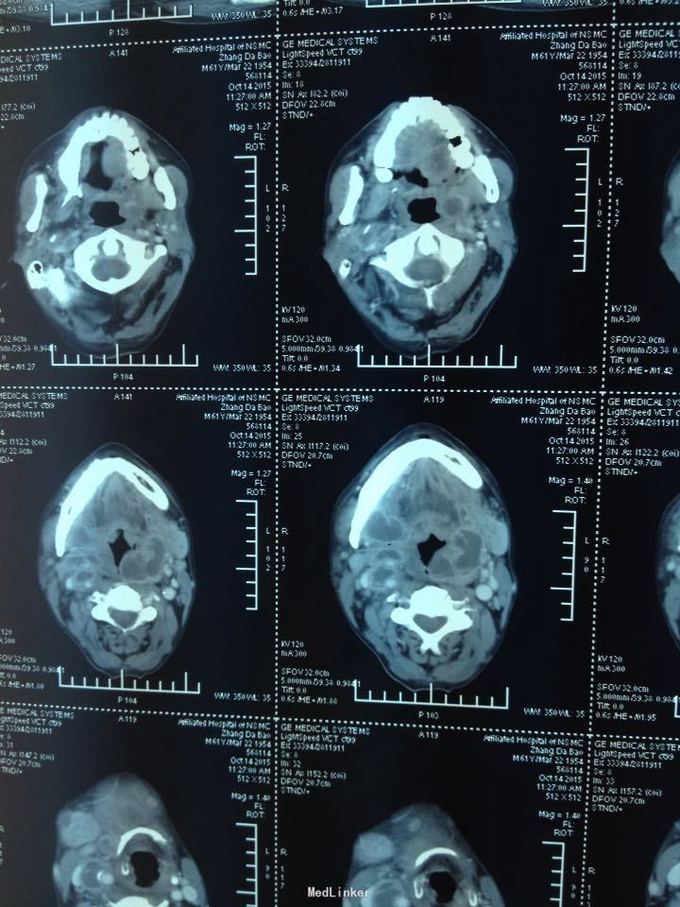

颈部肿痛10多天。10多天前无明显诱因出现颈部及颌下疼痛,肿胀明显,吞咽受限,无伴明显呼吸困难。无高热、寒战等。未特殊处理,上述症状渐加重。

双侧颈部肿胀明显,皮肤稍充血,皮温较高,可触及波动感,压痛明显,右侧为甚,咽部黏膜充血肿胀明显。

颈部多发脓肿。入院后完善相关检查,给予抗感染、对症支持治疗,并于急诊全麻下行颈部脓肿切开引流术,术中分离右侧颈动脉鞘,充分分离脓腔,充分引流。

颈部感染致脓肿多发是颈部感染的严重转归,而脓肿累及颈鞘时需要高度警惕,防止脓液腐蚀动脉血管,导致血管破溃大出血而致患者休克甚至死亡,需要充分告知患者及家属具体风险,手术中需要尽可能彻底分离脓腔,动脉周围脓肿需要谨慎分离。注意保护。